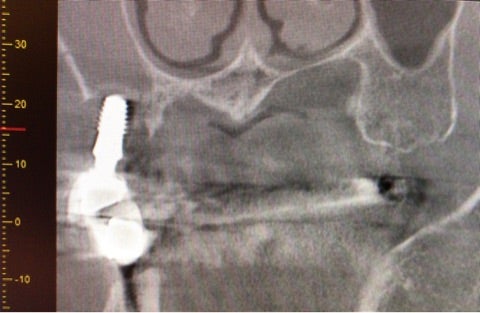

3次元的に精査する必要もある状態であったためCT撮影も行いました。

<CT画像>

▶︎CTからもインプラントを取り囲む顎骨の吸収が確認できました。